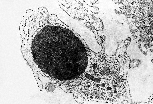

此巨噬细胞的另一切面经过核区和细胞中央,证实其溶酶体丰富。内质网虽不明显,但参与溶酶体酶的合成,并通过组成型分泌途径完成细胞膜的更新。 |